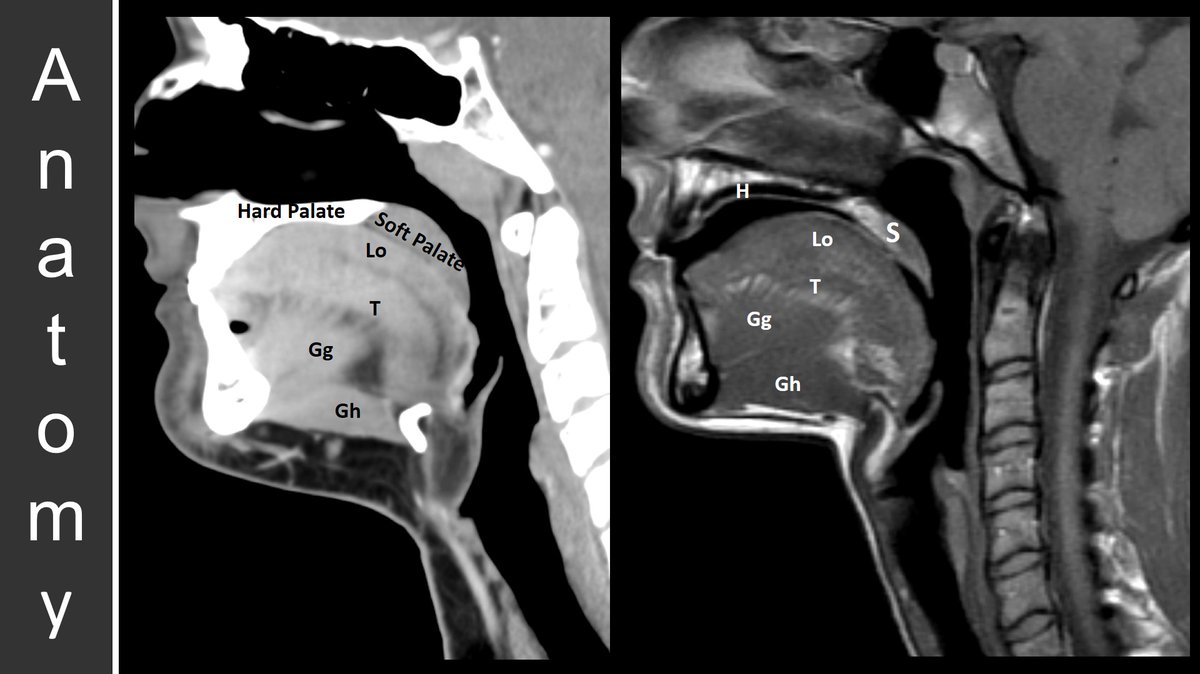

The oral cavity is anterior to the oropharynx & contains a # subsites including the lip, hard palate, oral tongue, FOM, RMT, max/mand gingiva, & buccal mucosa. Staging is initially based on📏 & depth of invasion (DOI) - which is seen at🔬 Graphics @ https://t.co/cstAFUowi2